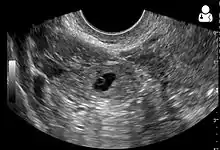

Transvaginal ultrasonography

An ultrasound showing a gestational sac with fetal heart in the fallopian tube has a very high specificity of ectopic pregnancy. It involves a long, thin transducer, covered with the conducting gel and a plastic/latex sheath and inserted into the vagina.[32] Transvaginal ultrasonography has a sensitivity of at least 90% for ectopic pregnancy.[5] The diagnostic ultrasonographic finding in ectopic pregnancy is an adnexal mass that moves separately from the ovary. In around 60% of cases, it is an inhomogeneous or a noncystic adnexal mass sometimes known as the "blob sign". It is generally spherical, but a more tubular appearance may be seen in case of hematosalpinx. This sign has been estimated to have a sensitivity of 84% and specificity of 99% in diagnosing ectopic pregnancy.[5] In the study estimating these values, the blob sign had a positive predictive value of 96% and a negative predictive value of 95%.[5] The visualization of an empty extrauterine gestational sac is sometimes known as the "bagel sign", and is present in around 20% of cases.[5] In another 20% of cases, there is visualization of a gestational sac containing a yolk sac or an embryo.[5] Ectopic pregnancies where there is visualization of cardiac activity are sometimes termed "viable ectopic".[5]

A pregnancy not in the uterus[33]

The combination of a positive pregnancy test and the presence of what appears to be a normal intrauterine pregnancy does not exclude an ectopic pregnancy, since there may be either a heterotopic pregnancy or a "pseudosac", which is a collection of within the endometrial cavity that may be seen in up to 20% of women.[5]